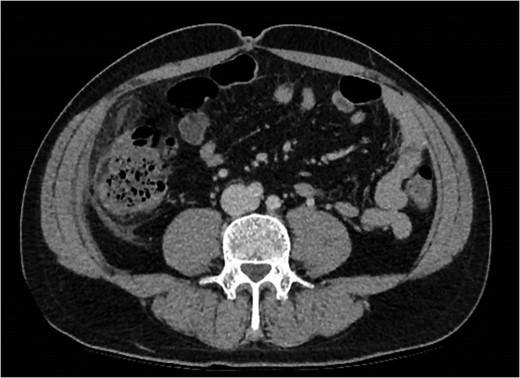

An initial differential diagnosis was made as cholecystitis. Appropriate intravenous antibiotics were commenced. An abdominal ultrasound demonstrated a thin-walled gallbladder without gallstones and a normal common bile duct caliber. There was however a trace of free fluid in the right iliac fossa. The sonographer was unable to identify a normal appendix. The following afternoon a CT scan of his abdomen and pelvis demonstrated fluid in the right iliac fossa as well as his rectovesicular pouch. The appendix was normal, but there was tissue stranding adjacent to the caecum and ascending colon to the tip of the liver (Figs 1 and 2).

Abdominal CT demonstrating soft tissue stranding anterio-lateral to the ascending colon/caecum without evidence of bowel wall thickening.